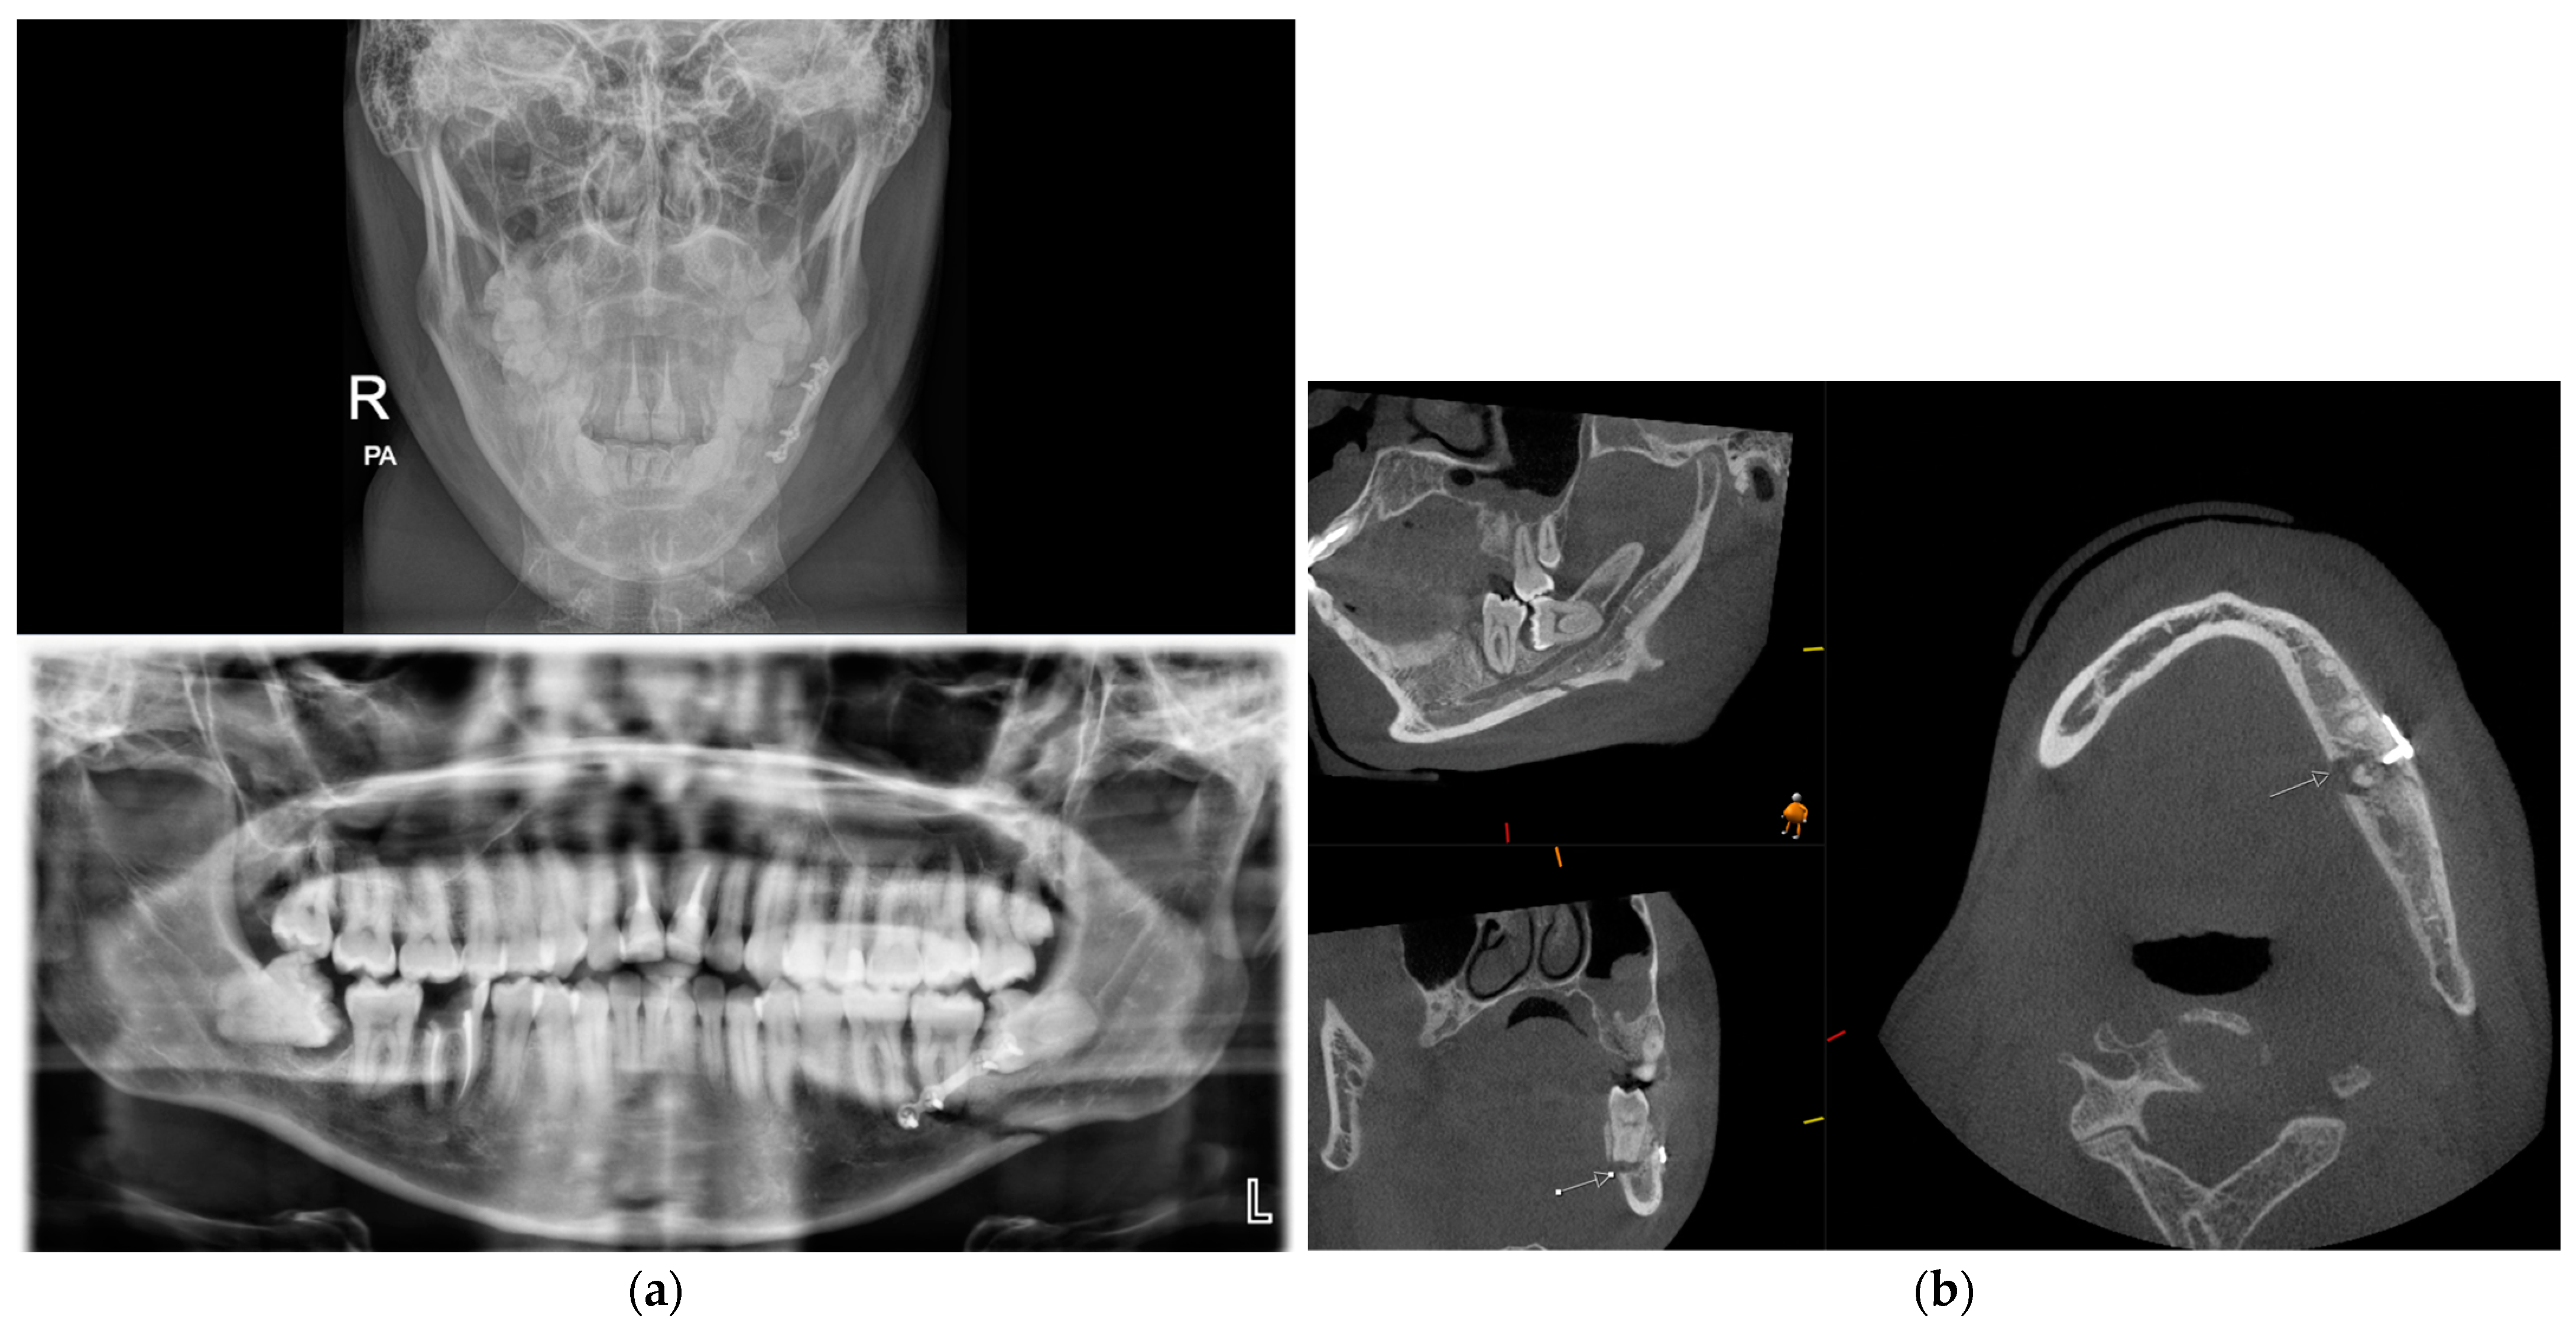

There is insufficient evidence to support the use of CBCT over conventional CT in the acute setting where there are concomitant facial or head injuries or where there is suspicion of muscle entrapment or retrobulbar haemorrhage. Figure 5 shows a CBCT coronal section of a patient with a right orbital floor fracture. The fat and muscle are indistinguishable when compared with the same slice in a conventional CT and therefore are not adequate for assessing muscle entrapment.

Figure 5.

CBCT (A) CT bone window (B) and CT soft tissue window (C) of the same patient, showing a right orbital floor fracture with soft tissue herniation. CT soft tissue windowing allows for differentiation between fat and muscle. On CBCT fat and muscle are indistinguishable. CBCT is suitable for assessment of the bony injury, but it is not possible to assess for muscle entrapment on CBCT. CT (D) at time of acute orbital trauma shows a right orbital fracture involving the floor, medial wall, and orbital roof. Soft tissue windows show inferior and medial rectus herniation. CT (E) prior to revision orbital floor repair shows that the medial rectus is herniating into a persistent medial wall defect (see arrow). CBCT (F) post-revision orbital floor repair shows that the new custom plate is well positioned with repair of both the floor and medial wall.

In the outpatient setting, in the absence of eye signs and a conventional CT, CBCT may be adequate for assessing the size of the defect and orbital volume in surgical planning. Furthermore, in this setting, mirror computational planning can be used and patient-specific implant (PSI) adapted free-hand on 3D-printed models. In the majority of cases, PSIs are acquired from conventional CT data. However, studies have shown the feasibility of using CBCT to construct orbital PSI [44]. At the time of publication, CBCT scans were not accepted for PEEKMilled implants, Titanium 3D-printed orbital and cranial implants by some medical technology companies (Synthes CMF CT-CBCT Scan Protocol) [45]. In our unit, CBCT is frequently utilised to assess the adequacy of orbital reconstruction (Figure 5).